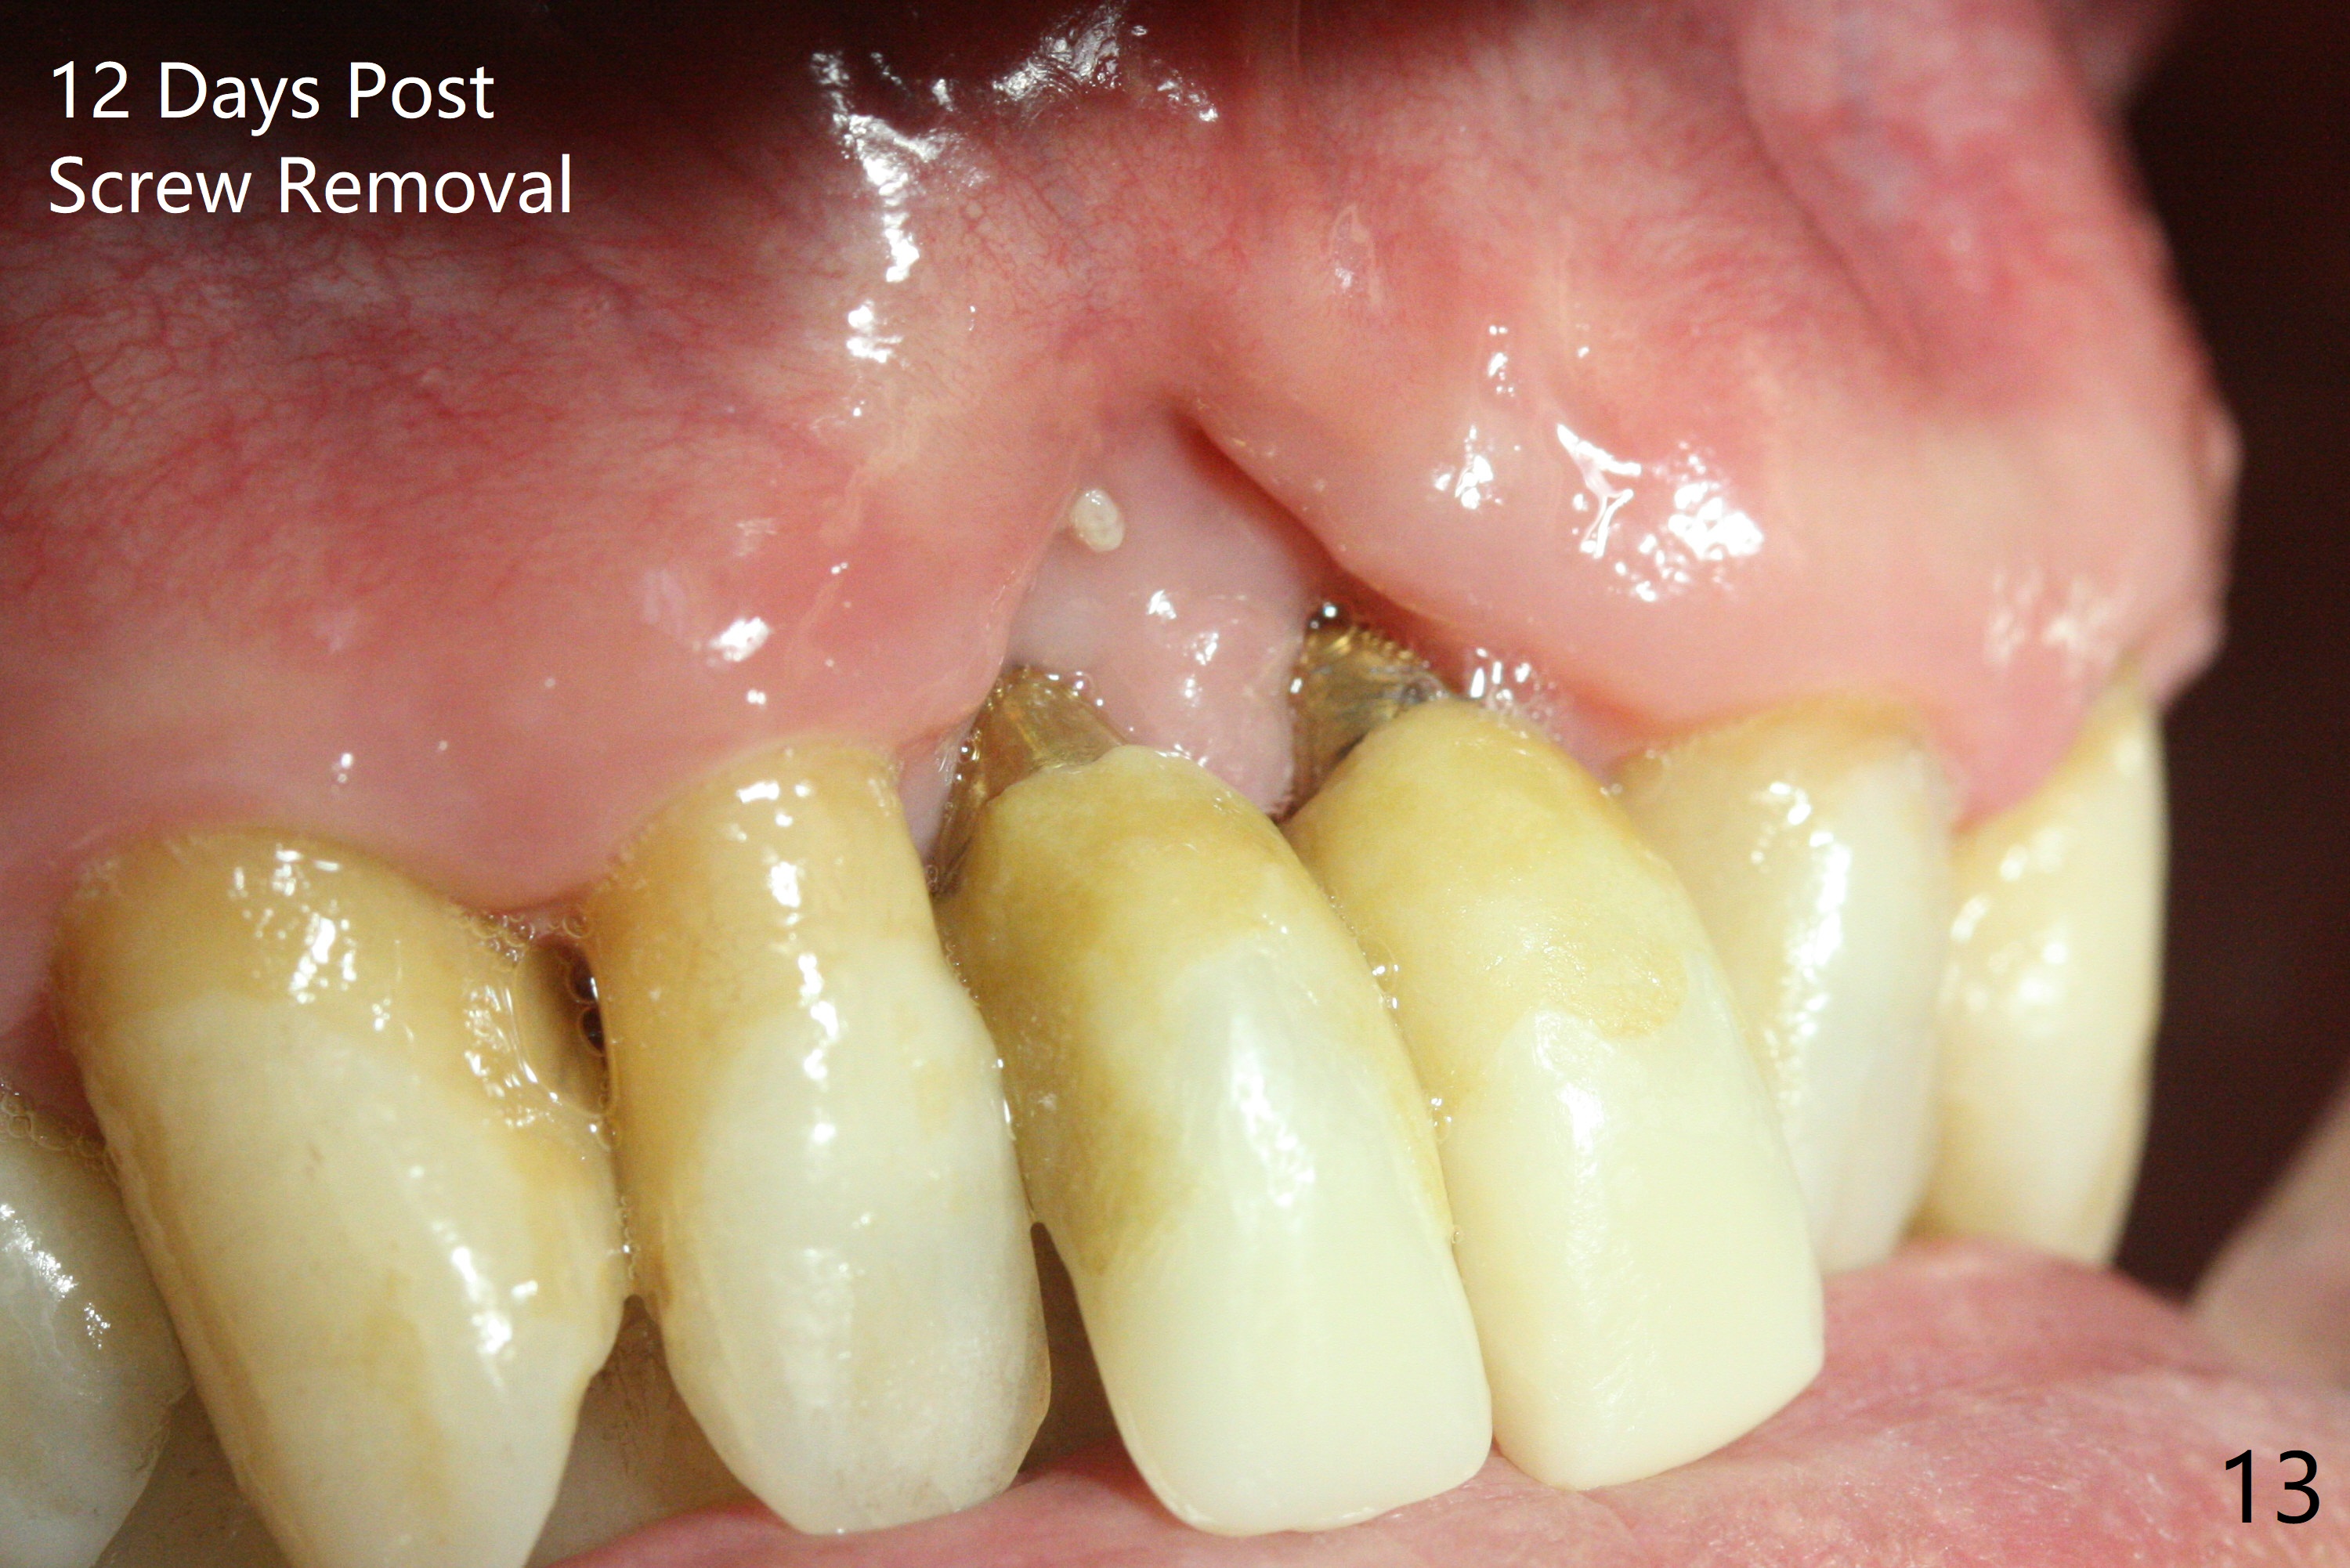

The gingiva remains recessive at #8 and 9 six months post immediate implant placement with bone graft (Fig.1). The buccal plate at #8 is particularly concave before (Fig.2 *) and after (Fig.3) abutment removal. The bony defect repair is assisted by placing a 4 mm tenting screw between the 2 implants (Fig.4) and placing allograft mixed with PRF (as putty) around the screw (Fig.5 (after replacement of the abutments)). The buccal contour improves because of the tenting screw and the bone graft placement (Fig.6 (as well as PRF and 6-month membranes)). The wound dehisces 12 days postop and immediately before leaving country for months (Fig.7). The sutures are removed, Osteogen plug is inserted (Fig.8) and periodontal dressing is applied (Fig.9). PA is taken to show the tenting screw (Fig.10 T). The latter is exposed 3 months postop (Fig.11,12). It appears that gingival graft is a must (Fig.13). Make a palatal stent, remove the temp with abutments and create a bleeding surface before harvesting a large piece of tissue. Connective tissue graft is done 5 months post bone graft (Fig.14). In fact there is no implant thread exposure. In fact the connective tissue graft does not survive. The abutments are re-prepared for pink porcelain (Fig.15). The bone loss is stable 1 year post cementation in spite of incomplete abutment seating (Fig.16). The soft tissue is nearly normal (Fig.17).